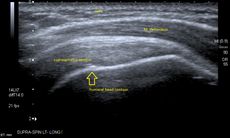

الموجات فوق الصوتية

التصوير بالرنين المغناطيسي